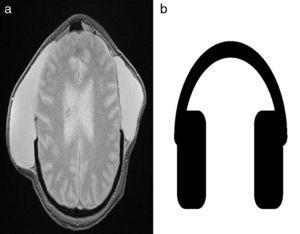

Por presentar episodios de cefalea con intensidad 8/10 en el posquirúrgico inmediato, se llevó a cabo una resonancia magnética nuclear (fig. 1a), en la que se visualizaron dos extensas colecciones homogéneas extraaxiales frontoparietales bilaterales (higromas) con intensidad de señal del líquido cefalorraquídeo. Su morfología era similar a unos auriculares (fig. 1b).

Dicen que la vida es más bella cuando se acompaña con una linda melodía…